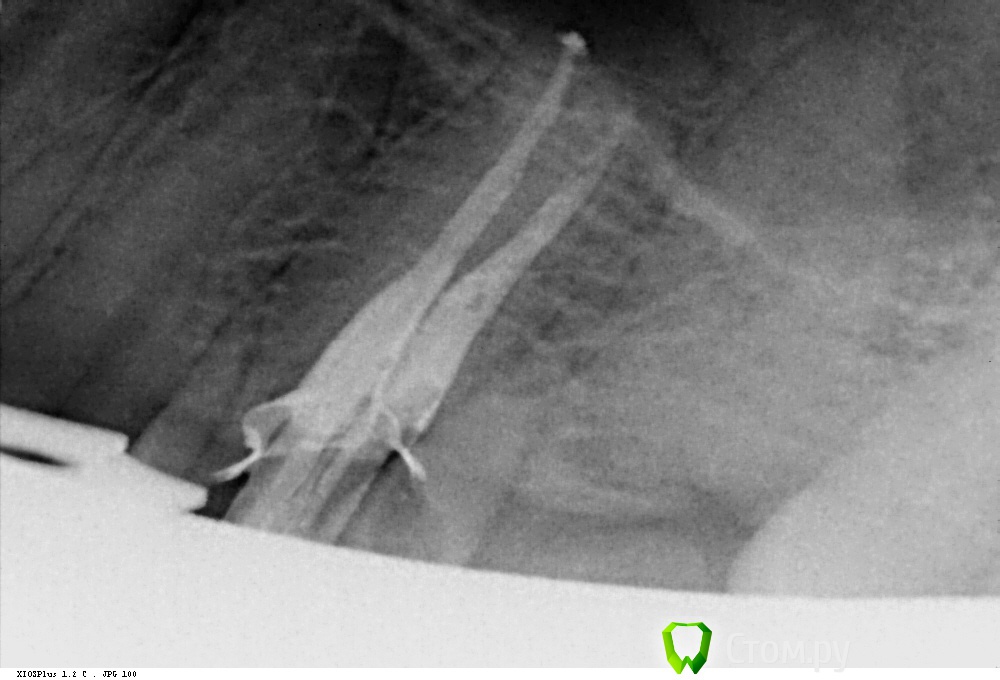

Shaid Опубликовано 28 января, 2014 Поделиться Опубликовано 28 января, 2014 Здравствуйте, уважаемые коллеги! Читаю форум с сентября 2011 года по настоящее время. За это время узнал больше, чем за всю учебу в ВУЗе. До сих пор не решался выложить что-либо на ваш суд. Но надо развиваться дальше и то подтолкнуло меня на создание данной темы, в которой я буду выкладывать удачные и не очень случаи из моей практики.Буду благодарен за любую критику. Итак, неделю назад пришла пациентка с желанием "подлечить все". После ОПТГ было решено начать с 4.6 зуба(кроме того, этот зуб начали лечить месяц назад, положив мышьяк, но не долечили). Глянув на снимок и ужаснувшись от длины корней этого зуба(30 мм по замерам оптг), я начал лечение, в первое посещение - ампутировал(да-да, он был живой несмотря на рентгенологич.картину) пульпу и создал доступ в каналы, сделал билд-ап из Vitremer. Во второе - первично прошел каналы и поставил Метапасту(не хватило времени). В третье, сколол клампом свой билд-ап мех, мед.обр-ка Протейперами до f2 насколько хватило длины инструмента, дальше - ручные. Мыл гипохлоритом, гуттой перемешивал. Обтурация - латералка .02 конусными. 10 Ссылка на комментарий

Shaid Опубликовано 29 января, 2014 Автор Поделиться Опубликовано 29 января, 2014 (изменено) Рис.1 Пульпит 2.5. Ничего необычного нет, просто понравился снимок) Возможно, кому-то покажется, что каналы перерасширены?Рис.2,3 Тоже пульпит пятерки. Тот случай, когда спредер залезает в канал, а 15 штифты - нет, гнутся , в результате чего картинка вызывает ассоциации, будто в каналы засунули по две дренажной трубки из хирургии. Изменено 29 января, 2014 пользователем Shaid Ссылка на комментарий